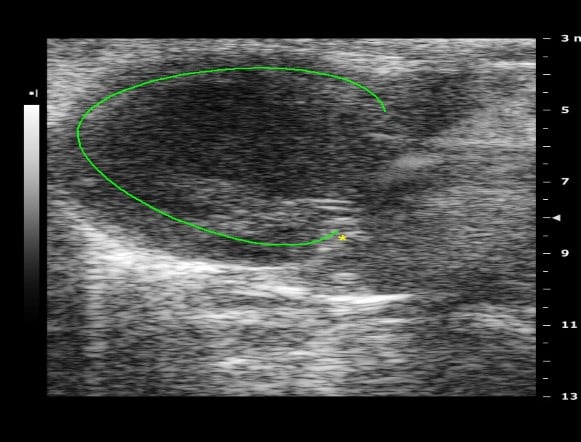

Normal Day-0 Preoperative Baseline Echo Data

Day-14 Post operative Chronic MI